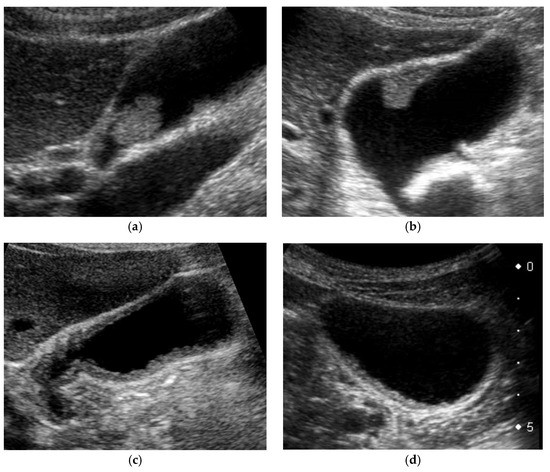

Figure 3. Morphological classification of US appearance. (a) Pedunculated GPL, (b) sessile (broad-based) GPL, (c) diffuse GWT, (d) focal GWT (all cases are GBCs).

US appearance of GB lesions is broadly divided into polypoid lesions (GPLs) and wall thickening (GWTs) (Figure 3). This classification is useful for differential diagnosis and is also used in US cancer screening [1].

GWTs include wall thickening of 4 mm or greater and focal presence of a partial inner hypoechoic layer of the GB wall even if the thickness is less than 4 mm [1] (Figure 3). Kim et al. [57] classified GWT of xanthogranulomatous cholecystitis (XGC) into diffuse (>50%) and localized (<50%) according to the extent of thickening. Thus, diffuse GWT was defined as a condition in which more than 50% of the GB wall shows wall thickening of 4 mm or more (Figure 3c), whereas focal GWT includes not only the wall thickening of 4 mm or more in less than 50% of the GB wall (Figure 3d), but also the focal presence of the inner hypoechoic layer, even if the wall thickness is less than 4 mm.